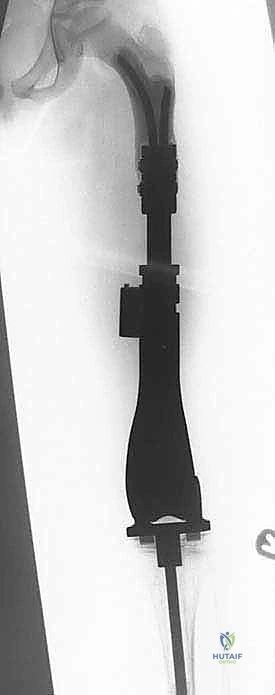

Once the resection level is determined, accurate measured radiographs and MRI cross-sections are transmitted to the prosthesis engineers. They will custom-fabricate or modularly assemble the implant to match the resected bone length precisely, accounting for the required joint line restoration and soft tissue tension. We currently utilize two main categories of expandable prostheses: minimally invasive (mechanical) and non-invasive (electromagnetic).

The Minimally Invasive Expandable Prosthesis (e.g., the JTS implant) is lengthened via an internal worm-drive mechanism. It requires a minor percutaneous procedure where an Allen key is inserted through a small stab incision to manually turn the mechanism. While highly reliable and mechanically robust, it carries a cumulative risk of infection with each lengthening procedure. Conversely, Non-invasive Expandable Prostheses (e.g., Repiphysis or Mutars Xpand) utilize an internal electromagnetic motor driven by an external magnetic coil placed over the limb in the outpatient clinic. This eliminates the need for repeated anesthesia and surgical incisions, drastically reducing the risk of secondary periprosthetic joint infection, though these devices are mechanically more complex and historically prone to internal mechanism failures.

Canal Preparation and Implant Trialing

Following resection, the remaining host bone canal must be prepared. In pediatric patients, the intramedullary canal is often narrow, necessitating careful sequential reaming. We must balance the need for adequate implant stem diameter (for mechanical strength) against the risk of iatrogenic cortical perforation or fracture.

A trial prosthesis is assembled and inserted. This is a critical step to assess limb length, joint line restoration, and soft tissue tension. The knee (or relevant joint) is put through a full range of motion. We assess for patellar tracking, varus/valgus stability, and ensure there is no impingement of the expansion mechanism. If the soft tissues are excessively tight, a slightly shorter modular segment may be required; if too lax, a longer segment is chosen to ensure joint stability.

Definitive Fixation and Soft Tissue Reconstruction

Fixation in the pediatric skeleton is challenging. While press-fit, hydroxyapatite-coated stems are utilized to encourage biologic fixation and extracortical bone bridging, cemented stems remain the gold standard in many centers due to the immediate stability they provide in compromised, irradiated, or chemotherapy-affected bone.

If cementing, a cement restrictor is placed, the canal is pulsatile-lavaged and dried, and third-generation cementing techniques (vacuum mixing, retrograde injection) are employed. The definitive prosthesis is impacted into place, ensuring correct version.